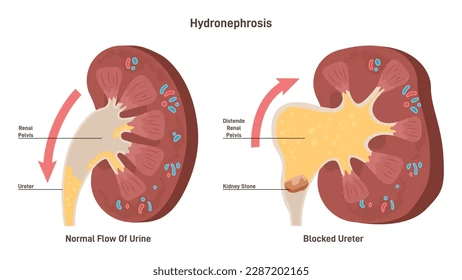

by Kimberly Allen ,RN Hydronephrosis means “water in the kidney”. It is a common...